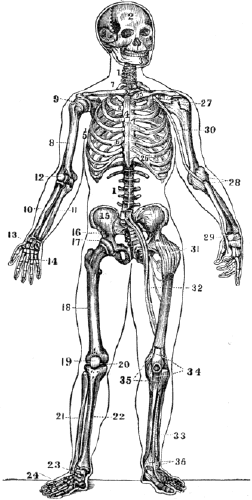

Fig. 28

Fig. 28. 1, 1, The spinal column. 2, The skull. 3, The lower jaw. 4, The sternum. 5, The ribs. 6, 6, The cartilages of the ribs. 7, The clavicle. 8, The humerus. 9, The shoulder-joint. 10, The radius. 11, The ulna. 12, The elbow joint. 13, The wrist. 14, The hand. 15, The haunch-bone. 16, The sacrum. 17, The hip-joint. 18, The thigh-bone. 19, The patella. 20, The knee-joint. 21, The fibula. 22, The tibia. 23, The ankle-joint. 24, The foot. 25, 26, The ligaments of the clavicle, sternum, and ribs. 27, 28, 29, The ligaments of the shoulder, elbow, and wrist. 30, The large artery of the arm. 31, The ligaments of the hip-joint. 32, The large blood-vessels of the thigh. 33, The artery of the leg. 34, 35, 36, The ligaments of the patella, knee, and ankle.

Note. Let the pupil, in form of topics, review the anatomy and physiology of the bones from fig. 28, or from anatomical outline plates No. 1 and 2.